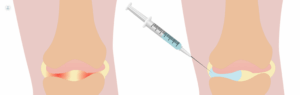

- Artrosis y desgaste articular

- Infiltraciones terapéuticas